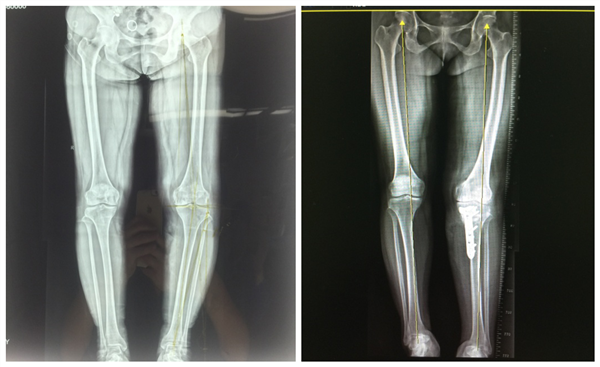

下肢全长片术前(左),术后(右)

骨一科党晓谦主任为其设计了关节镜下清理联合HTO的手术方案,根据下肢全长片规划出Fujisawa点,术前准确计算内侧截骨撑开角度。手术由骨一科时志斌副主任,樊立宏副教授,张子琦博士团队完成,首先通过关节镜在微创条件下进行半月板修整,去除引起疼痛和交锁的骨赘,对退变缺损的关节面软骨进行刨削清创后采用微骨折处理软骨缺损区,使髓内的干细胞生成纤维软骨覆盖软骨缺损区;然后于平台下方采用双平面张开截骨技术,撑开至合适角度矫正内翻,Tomofix钢板固定,术后膝关节内翻畸形明显矫正。目前患者膝关节疼痛明显减轻,功能恢复良好。